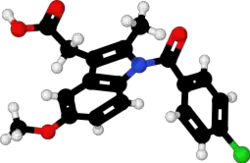

| Formula | C19H16ClNO4 |

| 3D model (JSmol) | |